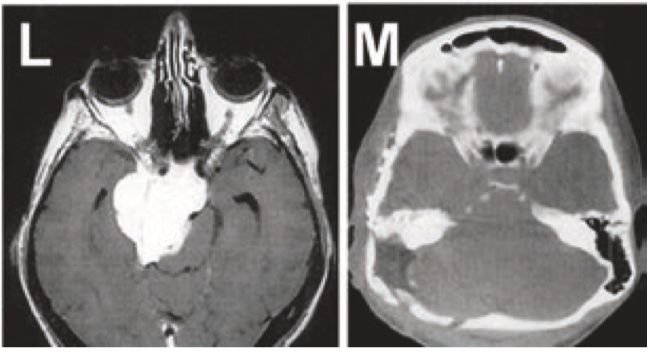

圖L+M:巖斜區(qū)腦膜瘤患者,術(shù)前術(shù)后的影像對(duì)比